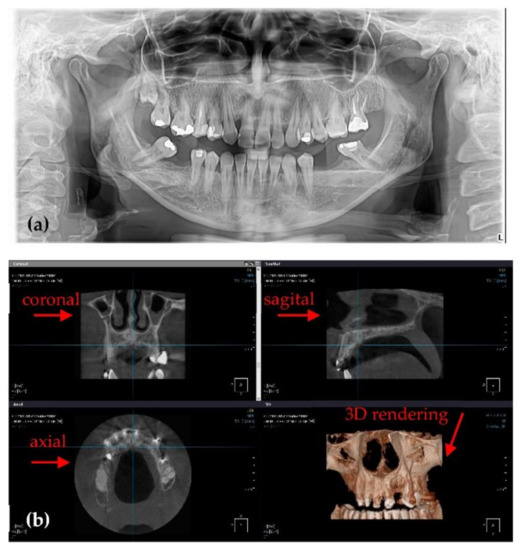

3.1. Optimized Protocol with OCT for X-ray Imaging Calibration. Panoramic Radiography

3.2. Optimized Protocol with OCT. 3D CBCT Calibration

3.3. Application of the Optimization Protocol on Patients (In Vivo)